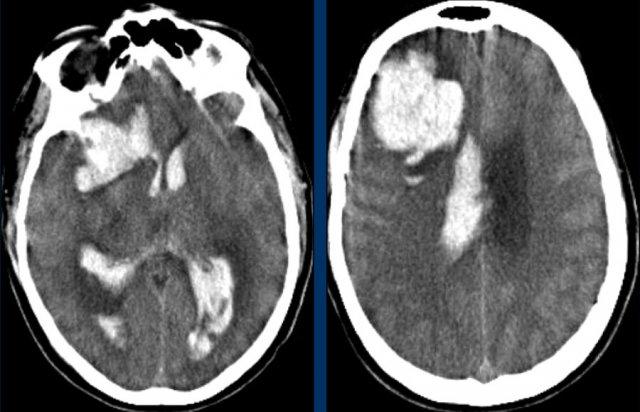

Chảy máu vào hệ thống não thất trong xuất huyết thùy não ít phổ biến hơn so với xuất huyết do tăng huyết áp do vị trí ngoại vi hơn.

Chỉ khi tổn thương rất lớn mới có thể gây chảy máu vào hệ thống não thất (hình).

Bệnh nhân này tử vong vào ngày hôm sau.

Không có chẩn đoán xác định nào được đưa ra, nhưng được cho là trường hợp CAA.